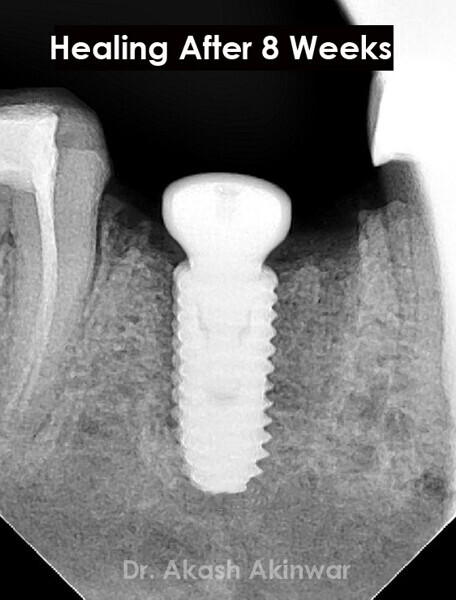

Flapless Single Implant Placement with Screw Retained PFM Prosthesis: Dr Akash Akinwar